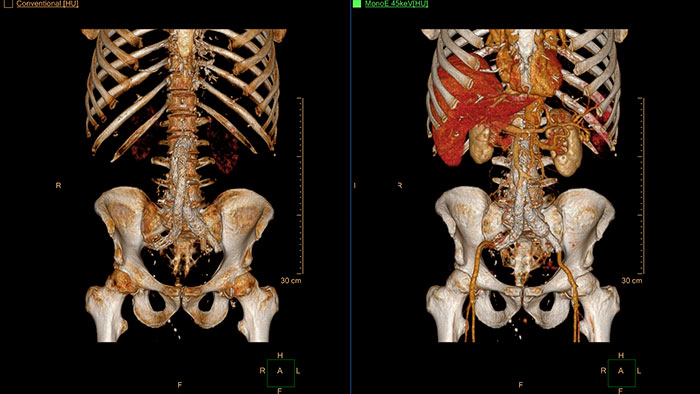

Multi Modality Advanced Vessel Analysis (AVA)

Comprehensive vascular analysis planning

Designed to examine and quantify different types of vascular lesions from CTA and MRA scans. It accommodates different modes of inspection, allows labeling different vascular lesions, and helps navigating through multiple findings.

Demonstrated to reduce the post-processing time by 50% when compared to manual Head & Neck CT angiography (CTA) analysis*.

Benefits

- Ability to choose which Head & Neck Bone Removal method to be used (Standard vs. Smooth).

- Customizable Volume rendering “smoothness” for the 3D Head & Neck vascular structure using a smoothness control.

* Ardley N et al. Efficacy of a new post processing workflow for CTA head and neck. ECR 2013 / C-1760.